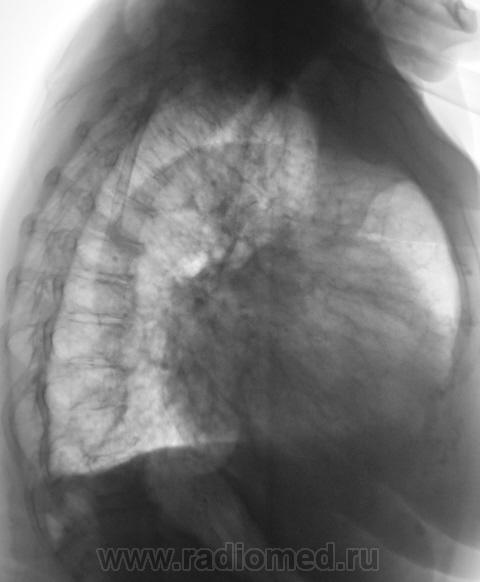

Следующий срез.

На рентгенограммах (в отличии от томо) на верхушке ничего не заметил. А так, похоже на митр. недостаточность.

Много, чего, всякого-разного мы не узреваем без "тёти Томмы". До сих пор, эта "добрая тетя", не оценена по - настоящему, а жаль...